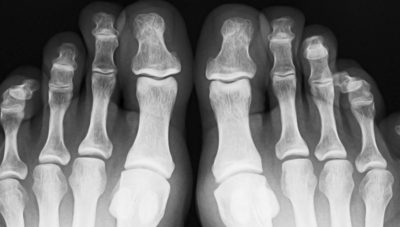

Diagnostic tools are key in pinpointing the exact cause of the heel pain. X-rays might be used to check for bone problems like heel spurs or fractures. Sometimes, diagnostic ultra-sound or an MRI is needed to get a detailed image of the foot’s soft tissues. These steps ensure that Dr. Titko can form an accurate diagnosis and craft a treatment plan tailored specifically to your needs, setting you on the proper path to recovery.